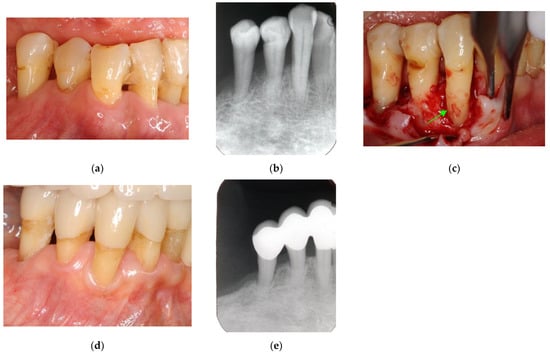

Figure 3. Clinical case 2. Female, age 35 yrs. (a) Intraoral view of the left maxillary incisor just before operation. (b) Preoperative periapical radiograph, with the “bone” defect presenting as a radiolucent area in both coronal and the middle of the root. (c) Flap retraction and debriding of the defect. (d) Photo of the extracted tooth, showing external root resorption (arrow).

Figure 4. Clinical case 3. Female, age 73 yrs. (a) Intraoral view of the lower right canine at baseline, presenting gingival swelling and pus discharge at the mesial pocket. (b) Preoperative periapical radiograph showing that the “bone” defect was due to advanced periodontitis. (c) Flap retraction and debriding of the defect, presenting the piece of cementum (arrow). Periodontal regenerative treatment with enamel matrix derivative was performed. (d) Fixed prosthesis inserted 5 years later, with healthy gingiva (PD < 2 mm). (e) Follow-up periapical radiograph.